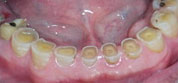

- ATTRITION

- 歯の咬耗(こうもう)

- 下顎前歯の咬耗

- かぶせ物の咬耗

- 奥歯の咬耗